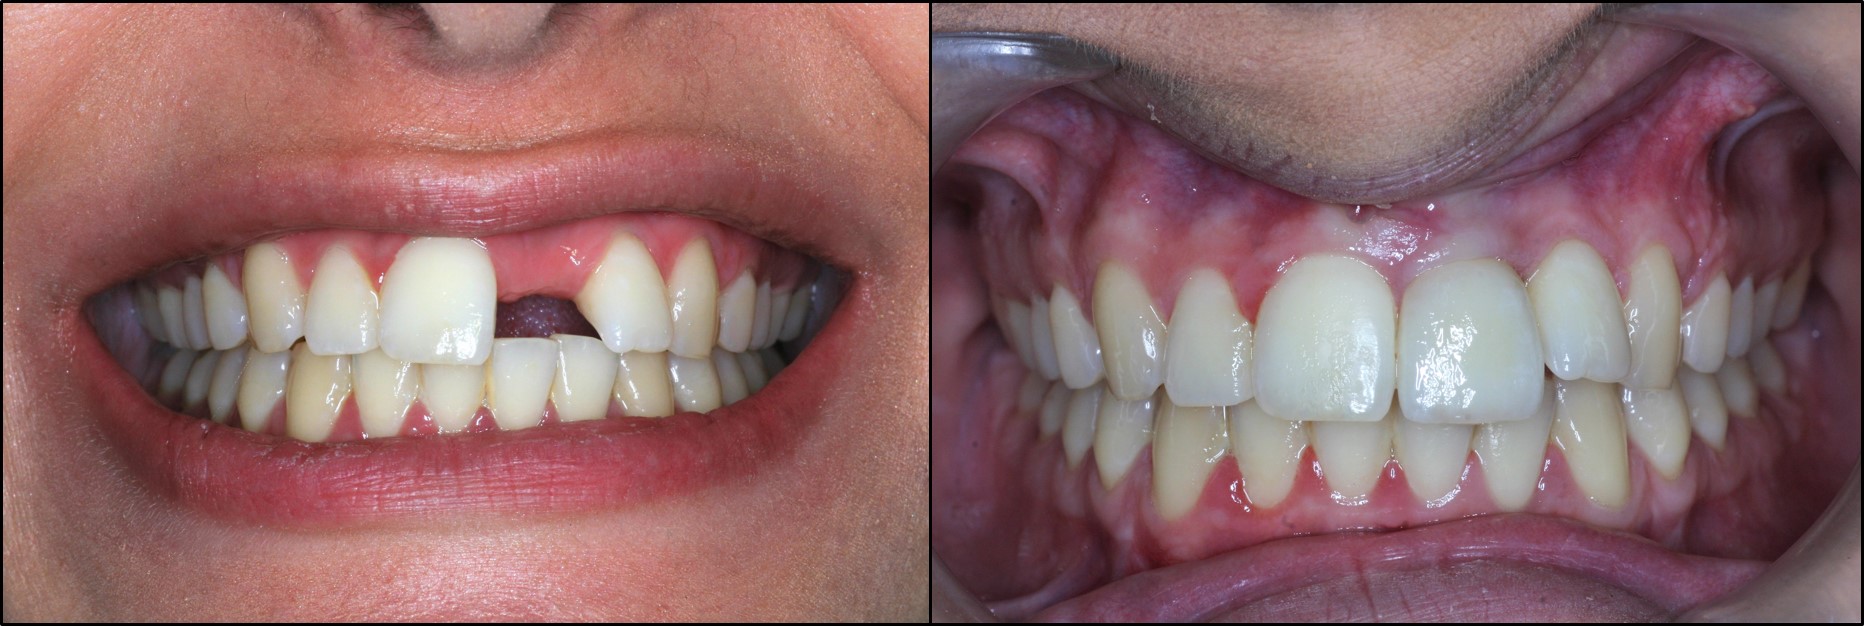

Η αποκατάσταση μονήρους ή τμηματικής απώλειας δοντιών στην πρόσθια αισθητική ζώνη της άνω γνάθου είναι ιδιαίτερα απαιτητική. Στόχος του χειρουργού και του συνεργαζόμενου οδοντιάτρου-προσθετολόγου είναι να δημιουργήσουν προσθετικές αποκαταστάσεις που να εναρμονίζονται αισθητικά με τη γειτονική φυσική οδοντοφυΐα και τους περιβάλλοντες μαλακούς ιστούς των ούλων. Για την επίτευξη του άριστου αισθητικού αποτελέσματος χρειάζεται σχεδόν πάντα να γίνει ανάπλαση με οστικά μοσχεύματα, ενώ κάποιες φορές απαιτείται συμπληρωματική διαχείριση της περίπτωσης με μοσχεύματα μαλακών ιστών (Εικόνα 10).